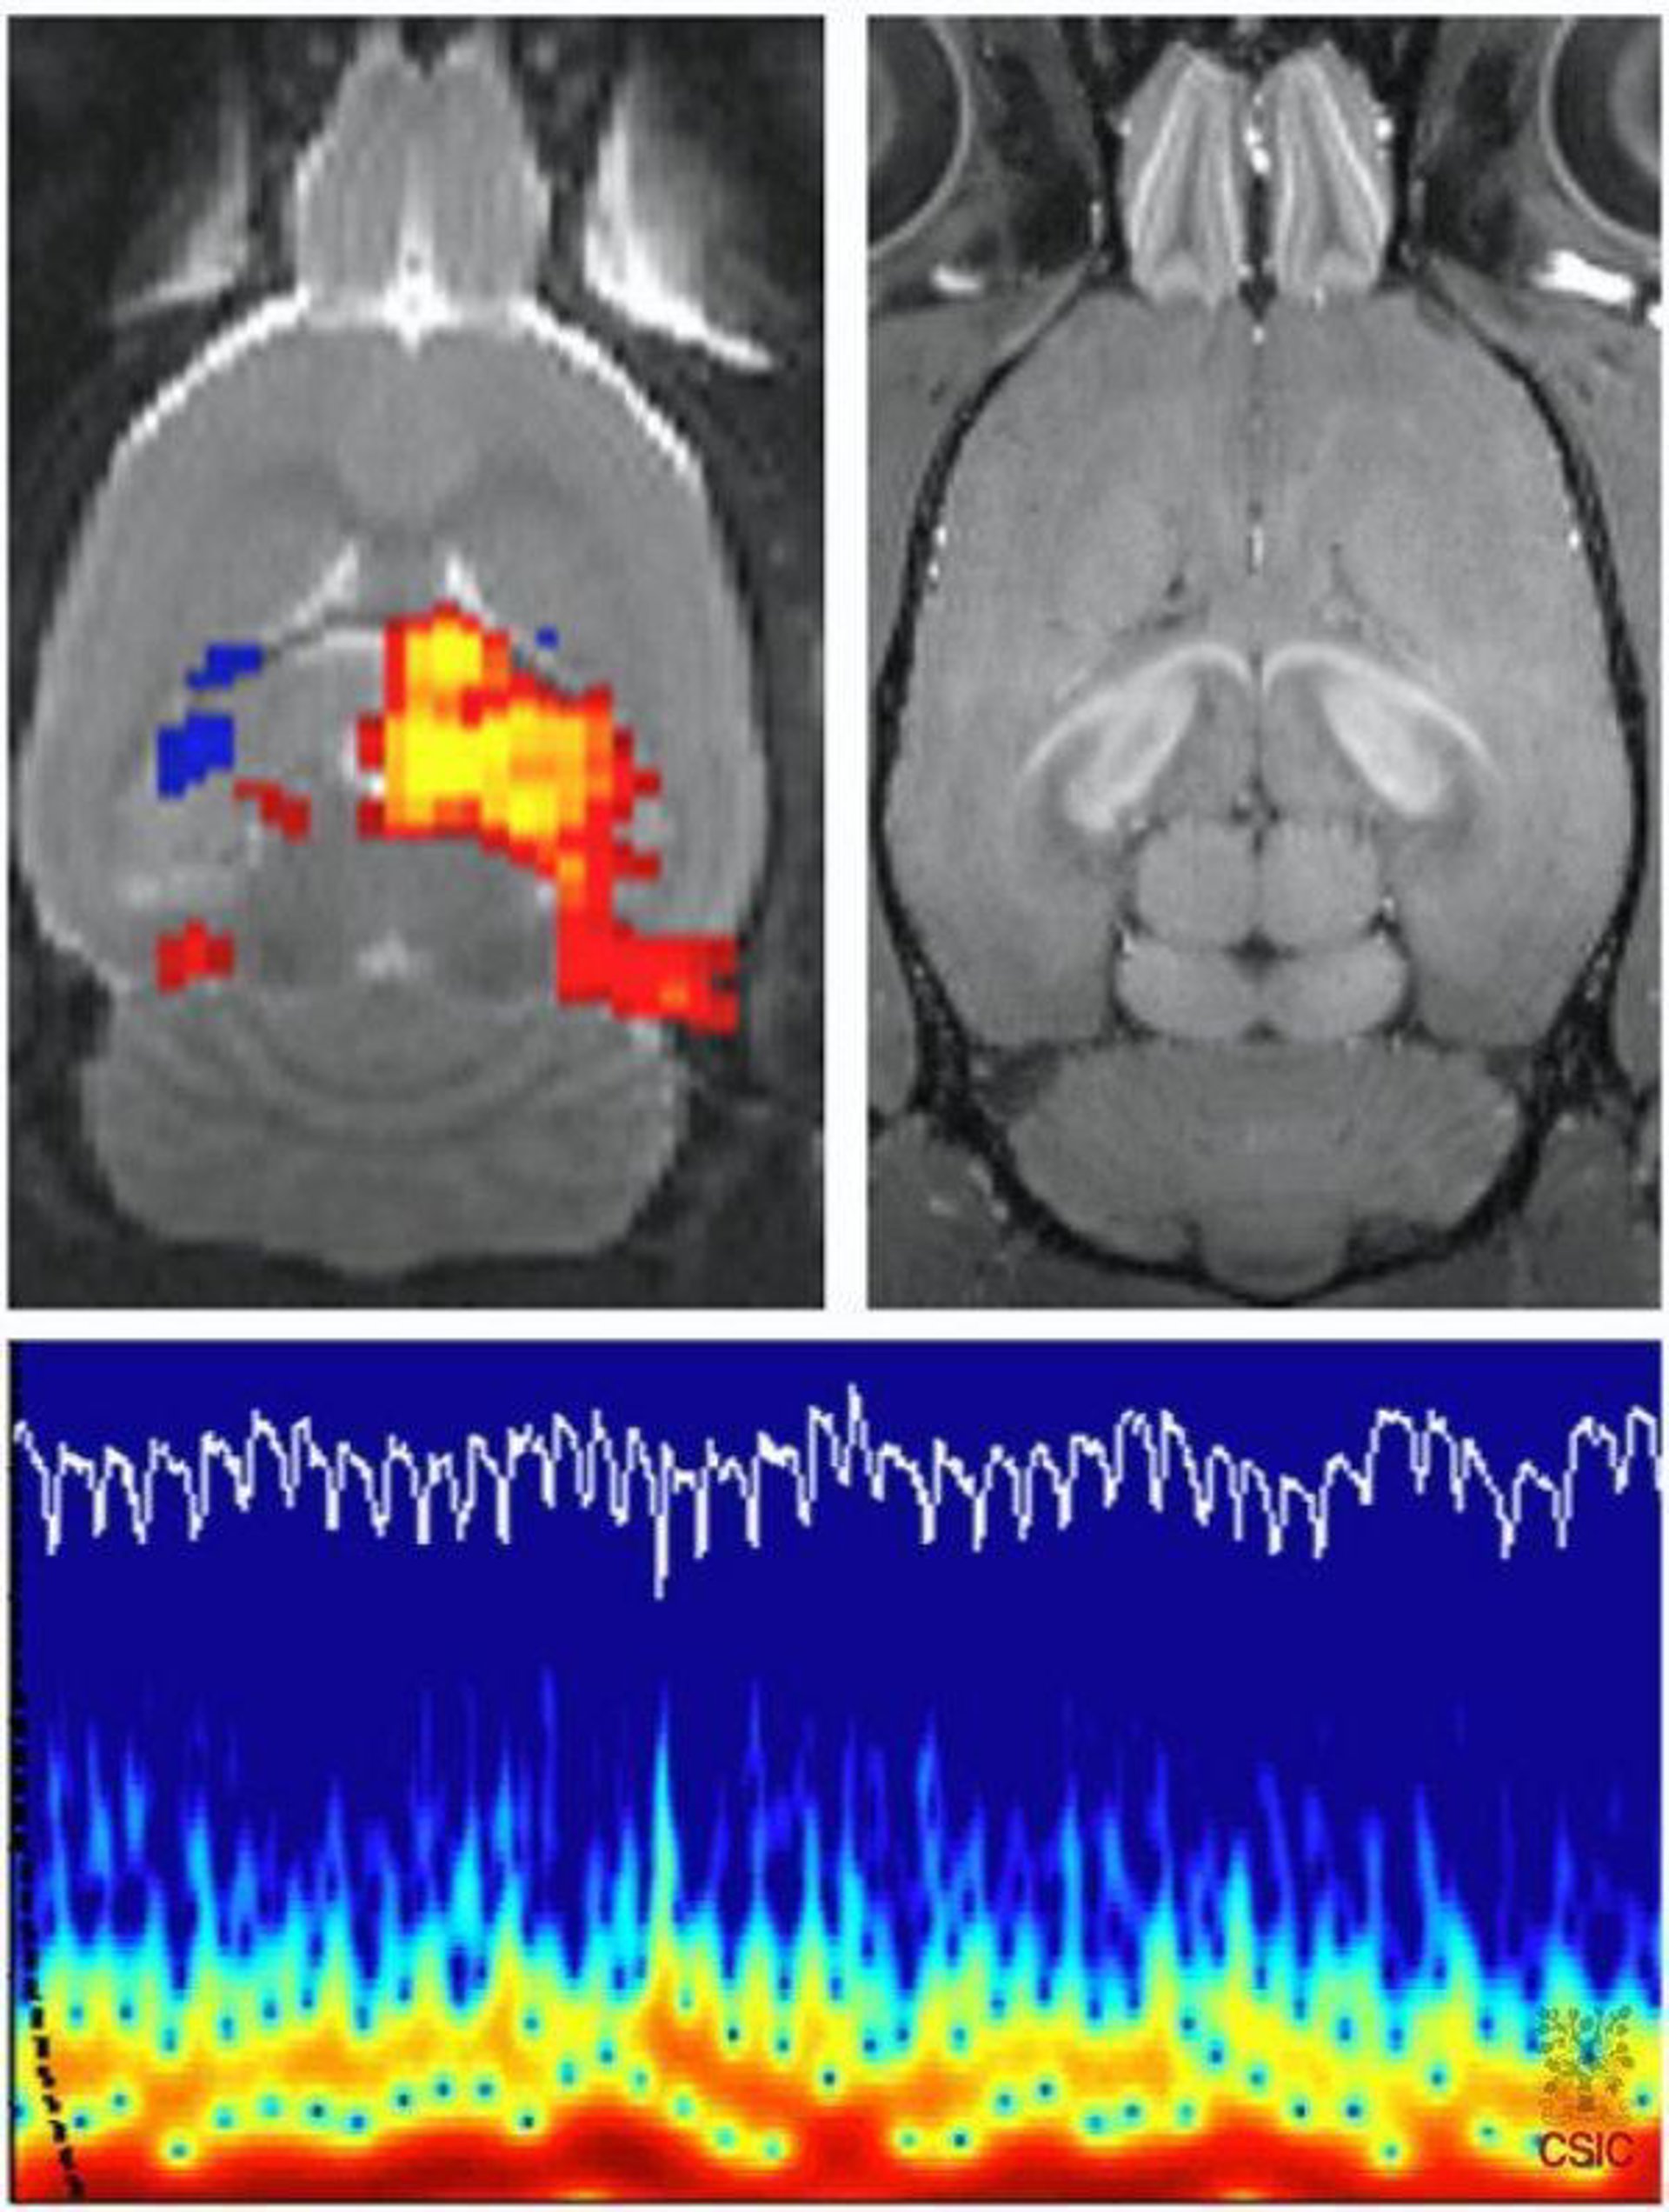

Los investigadores han utilizado imágenes de resonancia magnética funcional (IRMf) para estudiar la activación del cerebro y han descubierto que hombres y mujeres responden de forma diferente a los estímulos positivos y negativos.

Los investigadores reclutaron a 40 voluntarios diestros, 21 hombres y 19 mujeres, de entre 18 y 36 años de edad. Los voluntarios pasaron por exámenes de IRMf mientras veían imágenes del Sistema de Imágenes Afectivas Internacional (SIAI), un sistema de pruebas estándar muy utilizado que incluye varios miles de diapositivas de variados objetos e imágenes de la vida normal diseñados para evocar estados emocionales determinados.

Las imágenes se exponían en dos rondas. En la primera sólo se mostraban imágenes negativas y en la segunda imágenes positivas. Mientras veían las negativas, las mujeres mostraban una activación más fuerte y amplia del tálamo izquierdo, que transmite información sensorial hacia y desde la corteza cerebral, incluyendo los centros del dolor y el placer.

Los hombres mostraban más activación en la ínsula izquierda, que indica el estado fisiológico de todo el organismo y genera sentimientos subjetivos que pueden dar lugar a acciones. La información de la ínsula se transmite a otras estructuras cerebrales que participan en la toma de decisiones.

"La activación cerebral observada en las mujeres podría indicar una mayor participación del circuito neural, que se asocia con la identificación de los estímulos emocionales. La activación más pronunciada de la corteza insular en los hombres podría relacionarse con los componentes autonómicos, como la mayor tasa cardiaca o más sudoración, que acompañan el material emocional observado", explica Urbanik.

Mientras que veían las imágenes positivas, las mujeres mostraban una activación más fuerte y amplia en el giro temporal superior derecho, que participa en el procesamiento auditivo y la memoria. Los hombres mostraban una mayor activación en los lóbulos occipitales bilaterales, que están asociados con el procesamiento visual.